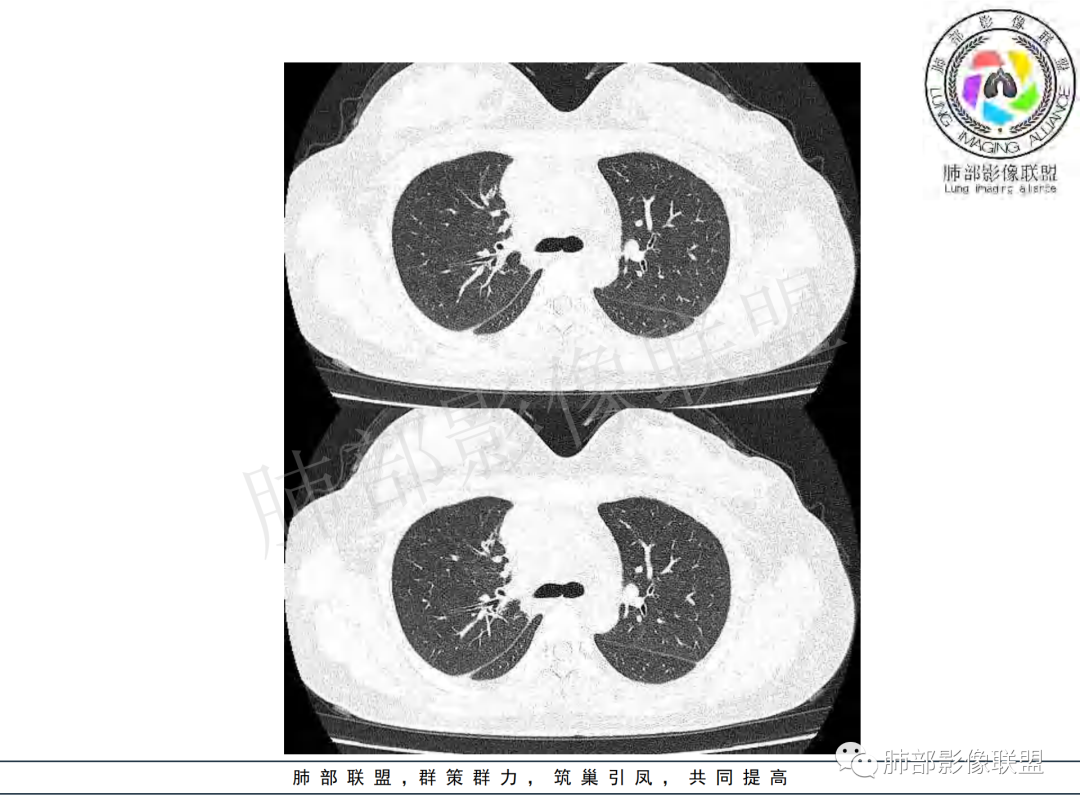

右肺门增大,远端花花草草不明显,支气管管壁增厚,纵隔淋巴结环形强化,年龄,病程,考虑炎性病变,结核可能,有个层面支气管截断,有强化,鉴别粘表。

纵隔多组及右侧肺门多发肿大淋巴结,部分融合,不均匀强化,内见斑片状坏死区及环状强化,后者坏死边界尚清晰,肺门区肿大淋巴结与肺组织边界不清,年轻女性,8个月病史,发热首发症状,考虑淋巴结核并向肺内侵及(破溃?),鉴别淋巴瘤

女,20,病程长达8月,发热、胸痛、右侧胸腔积液病史。胸部CT:右肺门旁不规则肿块影,右中间支气管腔内结节,纵隔多发淋巴结肿大;强化不均匀,灶性坏死灶,环形强化;右侧少量胸腔积液并局部肉芽肿样突起。年轻女性,长病程,多部位,考虑慢性炎症,结核?鉴别肿瘤。

年龄和病史比较符合结核,但是中叶支气管好像堵塞了,管腔有新生物,恶性肿瘤也不能排除,做一个支气管镜应该能确诊

青年女性,发热、胸痛、右侧胸腔积液病史,病程8个月。曾多次抗炎后均有好转。CT:右肺门旁肿块影,双侧胸膜结节,纵隔多发淋巴结肿大,边缘模糊;增强渐进性明显强化,纵膈淋巴结较彻底坏死灶,边缘环形强化。考虑结核,鉴别恶性肿瘤。

本例患者,年轻女性,慢性病程,多次抗感染治疗效果不佳,实验室检查示白细胞及中性粒细胞不高,不支持普通细菌感染,虽然肺泡灌洗液X-Pert检测阴性,结合患者胸部CT结核感染亦不能排除,胸部CT主要表现为右侧肺门及纵隔淋巴结肿大,仔细观察不难发现右中间支气管内新生物凸向管腔内,增强扫描,右肺门(10R)及纵隔淋巴结(2R,4R)明显不均匀强化,内部呈不规则低密度无强化区,被周边高强化区包绕(环形强化)的特点,首先应当想到纵隔淋巴结结核诊断。淋巴结分布亦不符合肺部恶性肿瘤迁徙途径。